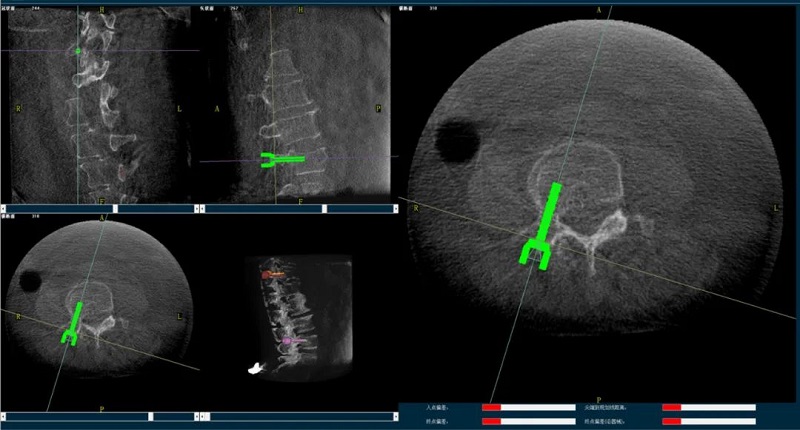

(1)首先使用普愛(ài)醫(yī)療三維C形臂采集胸腰椎病灶三維圖像,對(duì)傷椎進(jìn)行三維重建;

(2)醫(yī)生制定個(gè)性化的手術(shù)方案,在機(jī)器人導(dǎo)航界面上進(jìn)行路徑規(guī)劃;